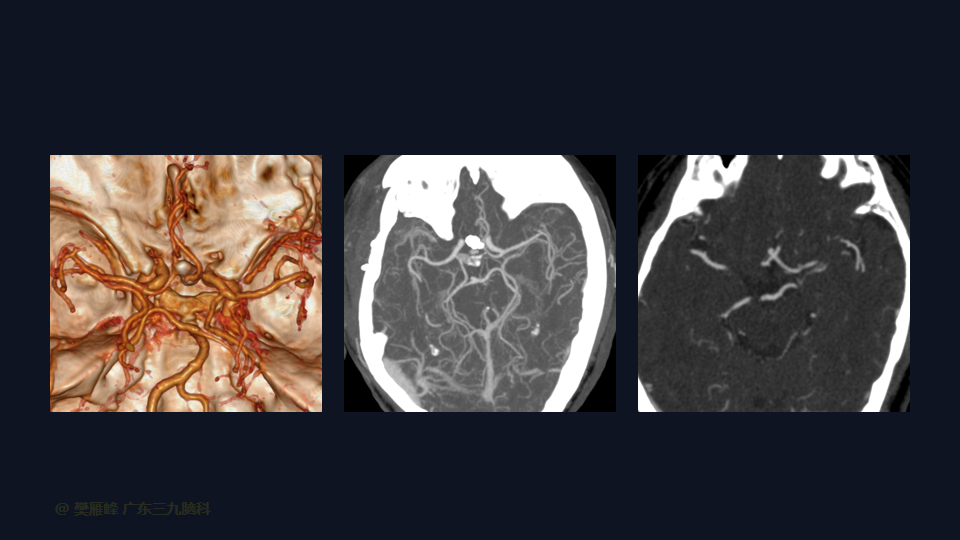

在这个二维手术视频中,展示了一种经翼点入路显微夹闭未破裂的前交通动脉瘤的方法。患者是一名61岁的男性,发现前交通动脉瘤1年较前增大,神经影像学显示前交通动脉大小约为3.6×3.3mm的囊状突起影。他接受了开颅手术夹闭动脉瘤的方法,术中血管造影显示动脉瘤完全夹闭。术后无新发神经功能。我们展示了细微的动脉分离技术和动脉瘤夹闭技术的细微差别和技术要点,以及手术技术。